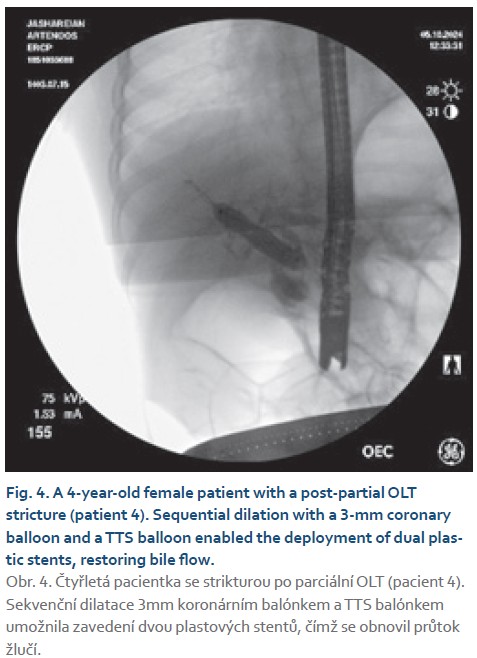

- patient 4: 4-year-old female with a post-partial OLT stricture;

- patient 4: sequential dilation with coronary and TTS balloons enabled dual plastic stent deployment in this pediatric patient;